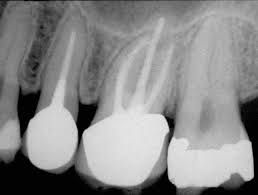

Typically it has a single root canal although it has been reported to have two root canals with a single apical foramen 13. Weine et al.3 reported that many treatment failures in the maxillary permanent first molar were related to the inability to locate and clean the mesiopalatal canal. The cusp of carabelli is heritable anatomical structur One hundred forty melamine teeth were prepared in three outline forms determined by the cusp that was removed: Probing defect on the mesiopalatal.

Introductionthe permanent maxillary first molar the maxillary first molar is the tooth located laterally (away from the midline of the face) from both the maxillary second premolars of the mouth but mesial (toward the midline of the face) from both maxillary second molars. the function of this molar is similar to that of all molars in regard to grinding being the principal action during mastication, commonly known as chewing. Mesial and distal are labeled in photos 2a and 2b. The mesial root exits the crown in a mesial direction and then gradually curves distally in the apical third. Cbct scan has proved to be a valid. The mesiopalatal cusp is the largest cusp; The results revealed that the mesiopalatal canals were present in 56.25% of the sections at 6mm from the root apex, and in 23.75% at 3mm from the apical limit. The results suggested the upper mesiopalatal cusp as a pivotal axis around which the upper first molar rotated. On other teeth it is the surface directed toward the first incisor (the surface adjacent to the tooth in front of it). The cusp of carabelli is heritable anatomical structur The correlation was evaluated using the spearman's correlation coefficient. Align needle with the plane extending from the corner of the mouth to the inter tragic notch 9. 3 16 the sharply defined distal ridge merges into the transverse ridge. Jump to navigation jump to search.